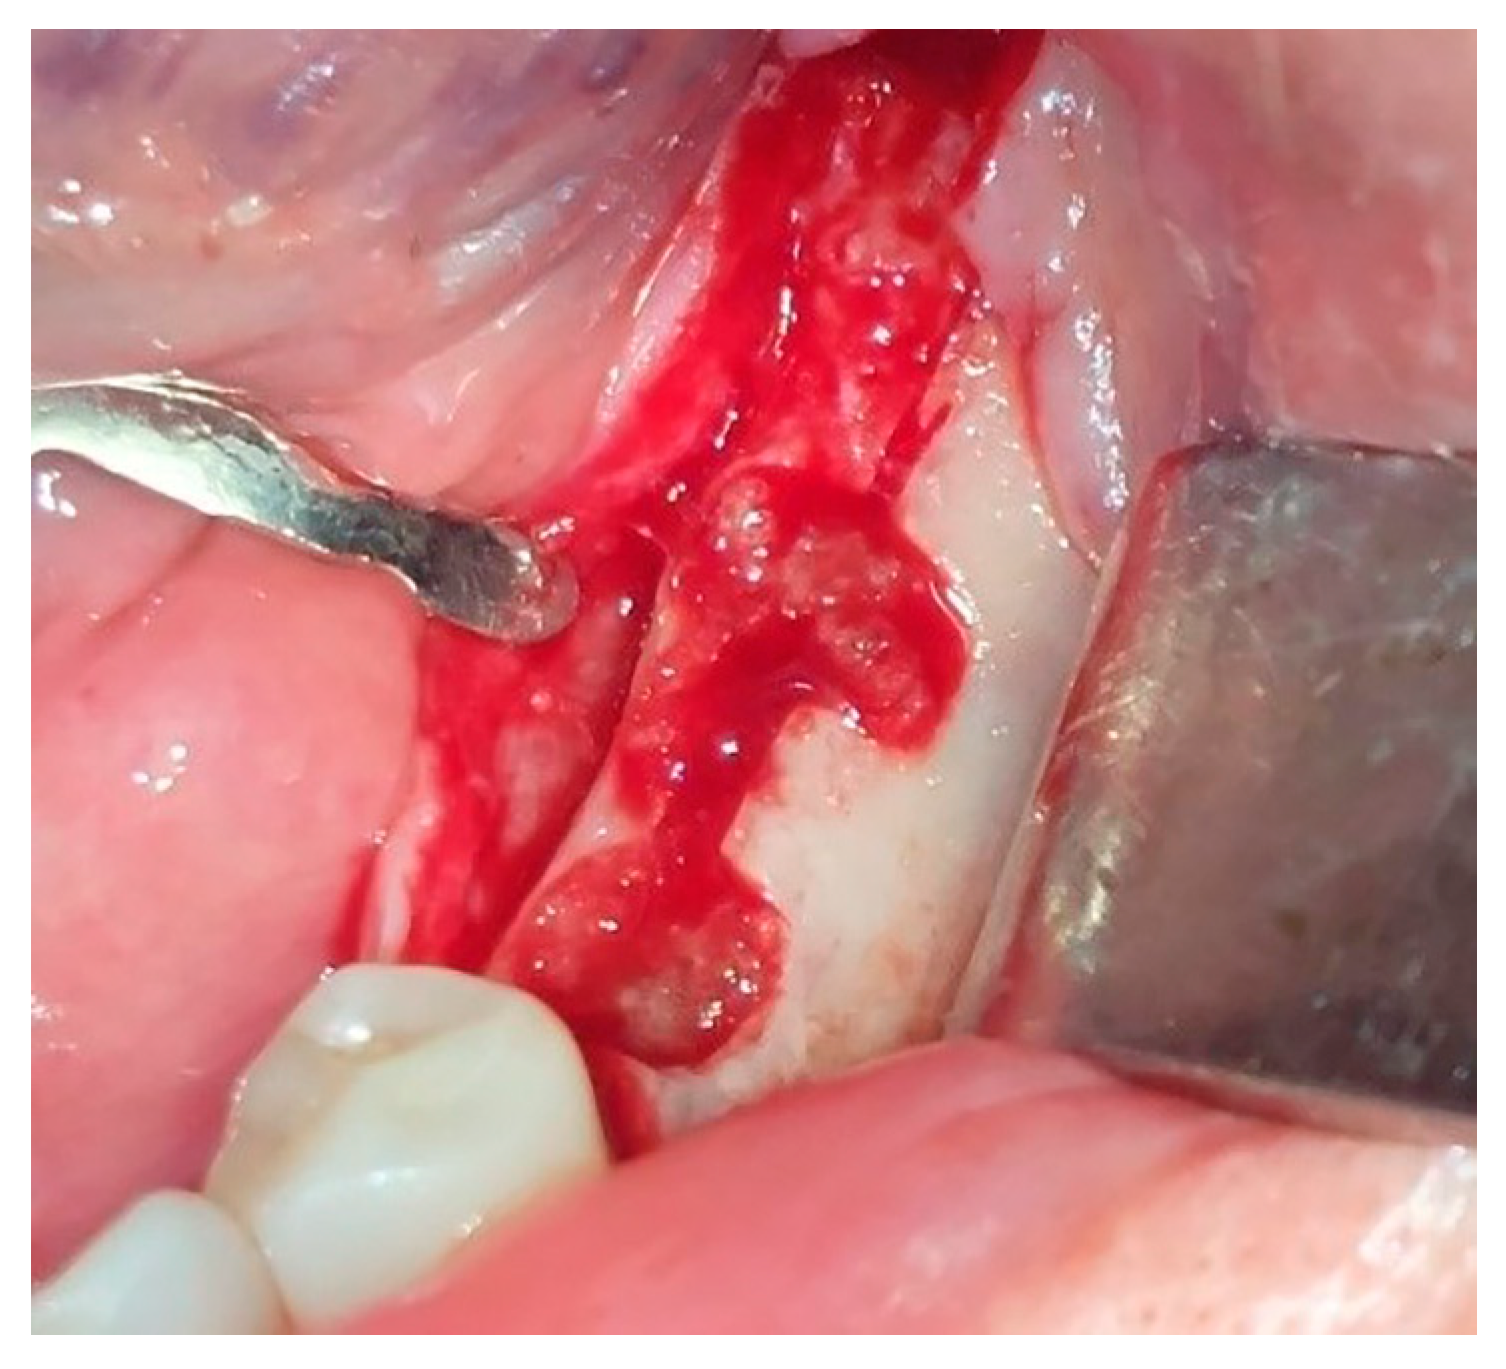

Figure 9. Dentin particles placed between buccal split from lingual bone lamella.

2.3. Dentin Chip Preparation

In Group III, the tooth indicated for extraction was extracted and milled in a dentin grinder (The Smart Dentin Grinder®, Tenafly, NJ, USA) and the gap between the cortical plates was filled with dentin (Figure 9). Periodontitis was the most common reason for extraction. After the extraction, the surface of the extracted tooth was cleaned of any remnants of soft tissue, composites, endodontic material, or decay using tungsten burs. There was no need to remove the enamel. Then, we placed the tooth into the chamber, set GRIND to a grinding duration of 3 s, set SORT to 10 s, and started the process. After the grinding was complete, the top drawer contained particles between 300 and 1200 µm and the bottom drawer contained particles smaller than 300 µm. We mixed the dentin particles together and proceeded with disinfection. The graft was completely soaked with Dentin Cleanser and left for 5 min. The cleanser removed all organic substrate and left the graft bacteria-free. Sterile gauze was used to dehydrate the cleanser. Then we applied Dentin Wash (phosphate-buffered saline) to completely cover the graft, immediately dehydrated it with fresh sterile gauze, and repeated this step twice. After that, the dentin graft was ready for use and we inserted it into the gap created with expanders between the buccal and oral bone lamellae.